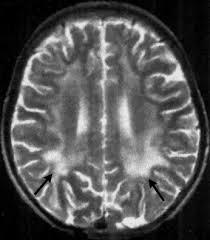

- SSPE, also known as Dawson disease, is a progressive, disabling, and deadly brain disorder related to measles (rubeola) infection.

- This response leads to brain inflammation (swelling and irritation) that may last for years.